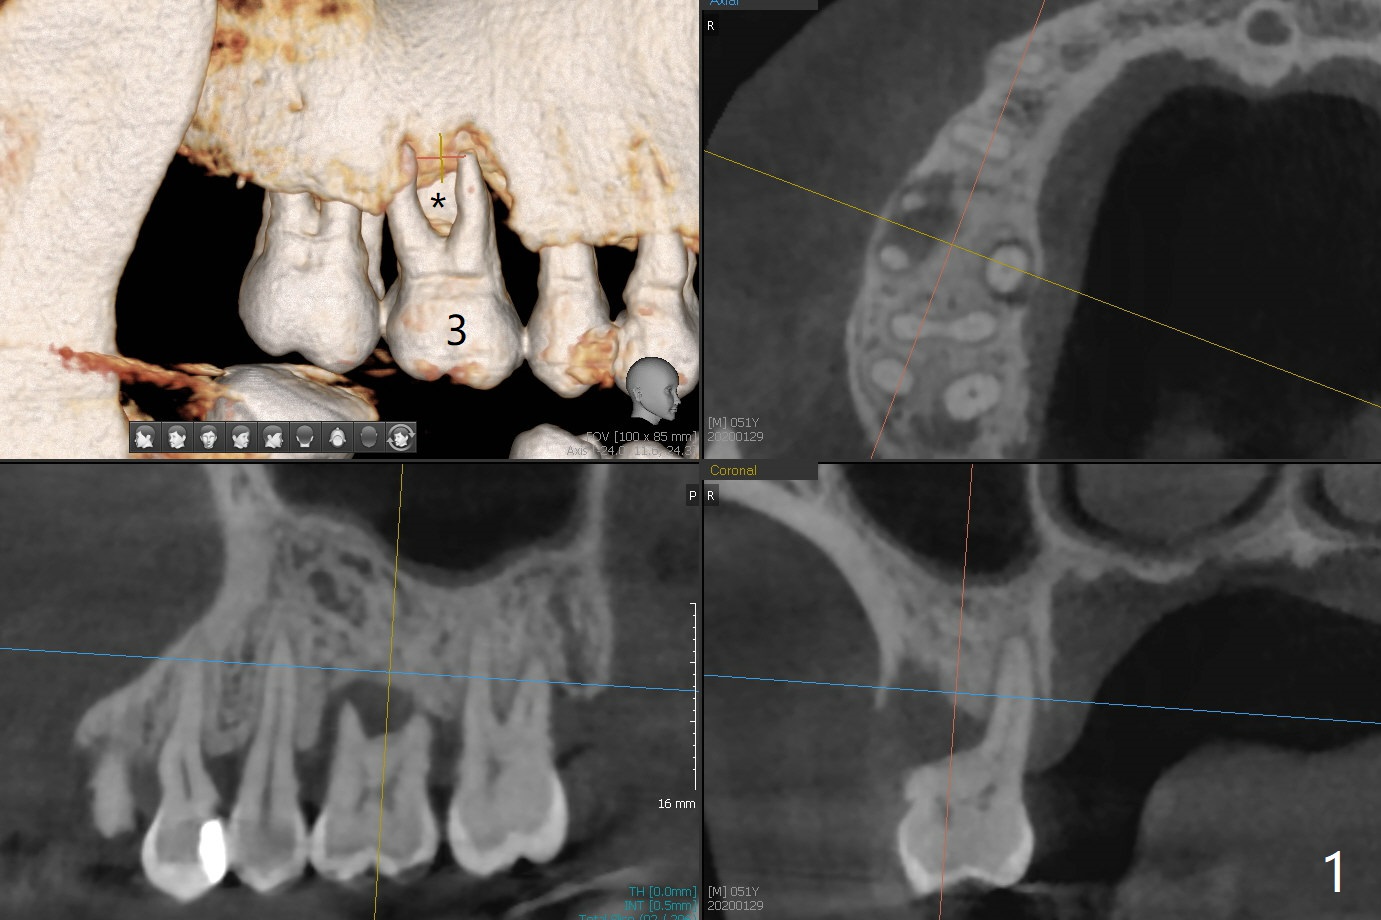

One month post cementation of the crown of #30, the opposing tooth (#3 in Fig.1) becomes symptomatic as related to the buccal furca (*). After periodontal maintenance, Arestin is placed at the furca. If the treatment does not achieve pain relief, the tooth will be removed with immediate implant free hand. Following 1.6 mm drill in the septum (Fig.2), insert its own parallel pin for PA (trajectory). After use of Marking Drill, use 4.3 mm Magic Drill with 9 mm stopper, followed by sticky bone and 4.5x10 IS dummy implant (crest level) for sinus lift (2nd PA). With confirmation of lift, insert the 1st piece of PRF membrane (small), more sticky bone and dummy. The definitive fixture will be 5x10 or 11 mm. Pack more sticky bone around the implant, especially buccal. Insert collagen dressing in the apical portion of the palatal socket if necessary. A temporary abutment (non-hex) should be easily placed. Insert 2nd piece of PRF membrane around the immediate provisional for complete seal. If it is still insecure, place periodontal dressing. In fact, the tooth is mobile with more severe bone loss 6 months later (Fig.3). Impression is taken for guide. 53 years old Male